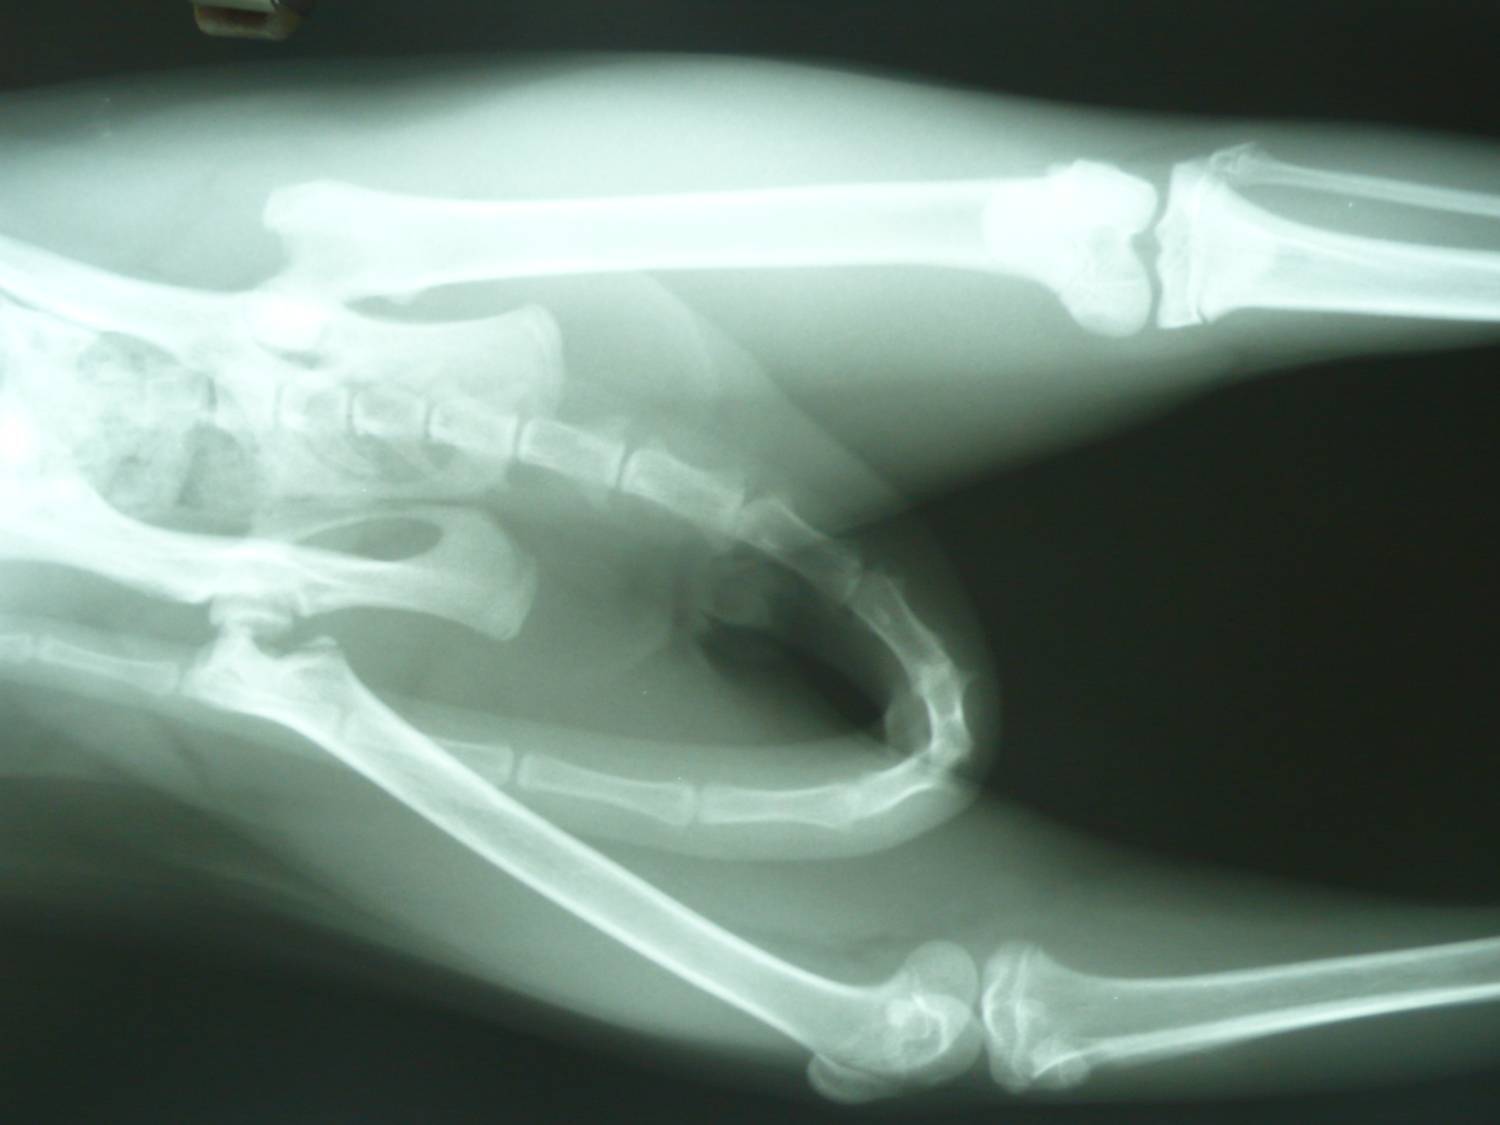

主題: 股骨骨折黑白貓救援 申請者姓名: Akimasa Tu 花色: 申請日期: 2013-01-10 00:10:15 申請者部落格: 申請者臉書網址: https://www.facebook.com/akimasa.tu 所在縣市/合作醫院: 台北市/長沁動物醫院 治療費用: 14700元 需求人數: 16人 已結案 (2013-08-06 13:43:00) 報名人員: Alumi Lu(已付款)、阿麥麥(已付款)、J2(已付款)、Amy(已付款)、Yu-Chen Lee(已付款)、Tsai Wan June(已付款)、Carolyn(已付款)、chiawei(已付款)、收夕(已付款)、何春生(已付款)、黃咪咪(已付款)、Shirley(已付款)、Coco Cheng、鄧伃絜<代馬媽媽捐款)(已付款)、鄧伃絜(已付款)、Tabby Jane(已付款)、洪嘉淑、momo(已付款)、 候補人員: 動物病情說明: 這貓生活在大同區圓環附近的某公園中,某天餵養他的愛媽志工發現,

他無法正常行走,只能三隻腳跳著活動,愛媽電話請我幫忙,貓咪也還

算親人,將他送醫,照X光後發現,原來他的股骨,不明原因骨折了。